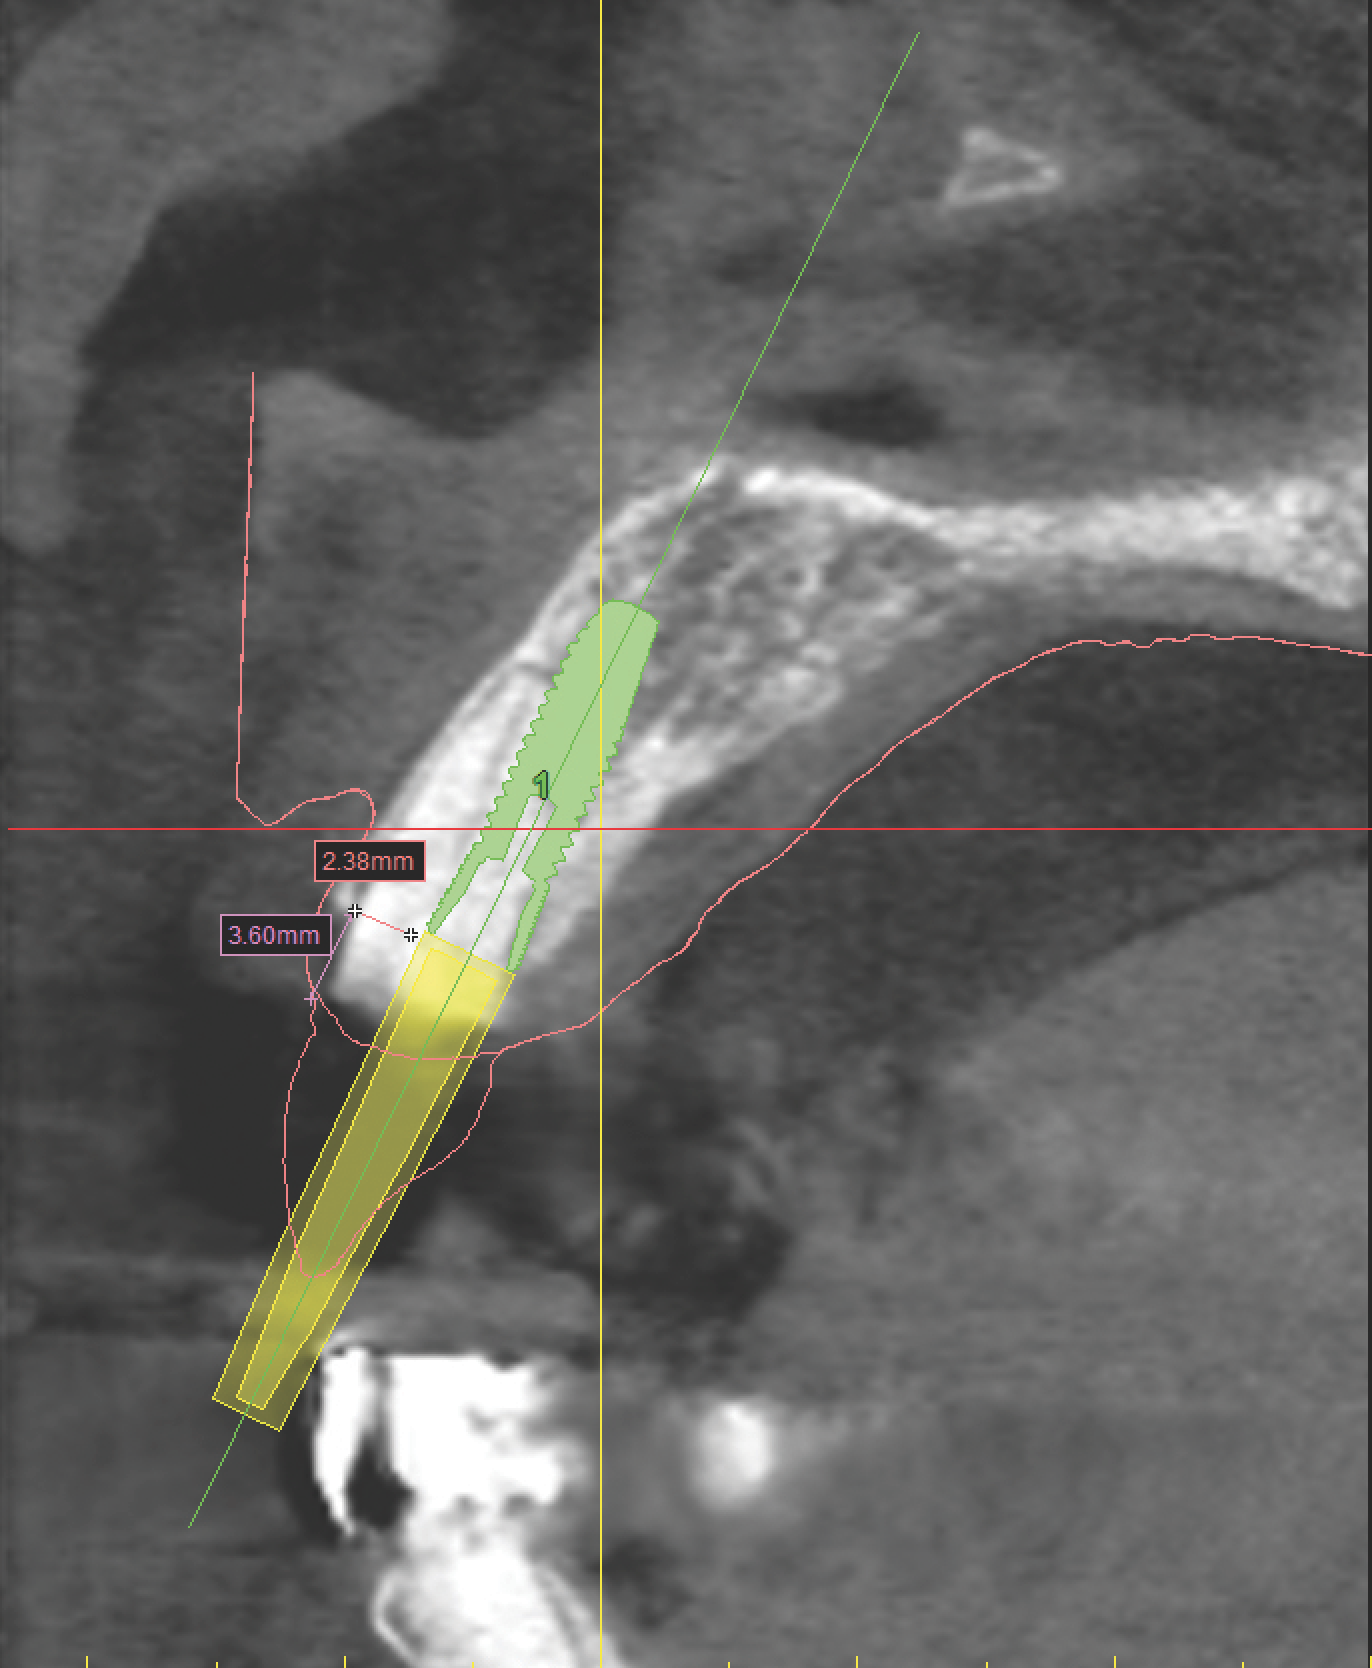

With all of this needed information relative to the pre-operative condition and proposed final tooth position, the treatment moved into the assessment and planning phase. The CBCT revealed an intact buccal plate anterior to the root of tooth No. 8 with adequate bone surrounding the area in all dimensions. Because of the favorable bony contours, an immediately placed implant was decided upon and planned in the software. The CEJ of the proposed final tooth location was identified and an OsseoSpeed EV 4.2 C - 11 mm implant (Dentsply Implants) was planned 3 mm apical and 2 mm lingual to that landmark12 to assure adequate biologic and prosthetic space for the final restoration (Figure 3 through Figure 5). A Simplant SAFE Guide was selected and ordered to convey all of the positional parameters of the final implant position, including depth control and implant timing.